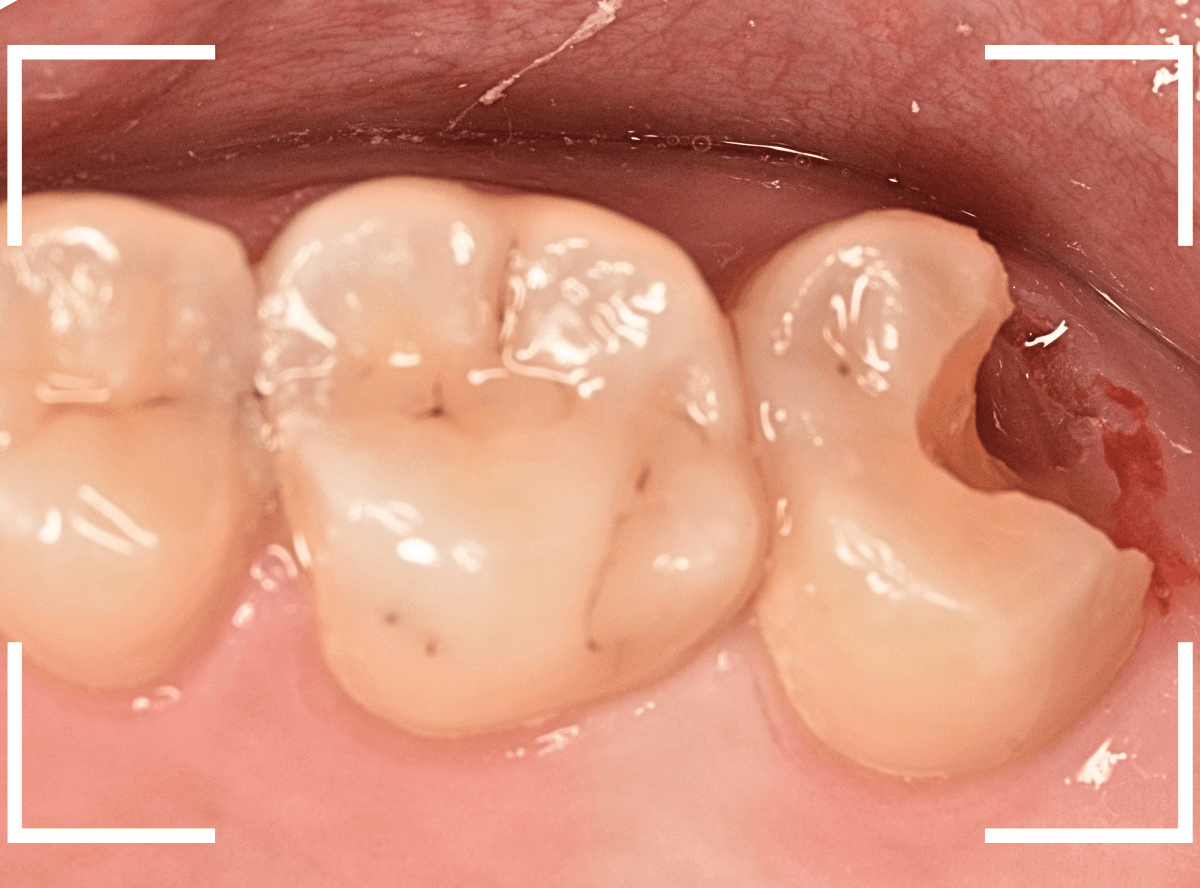

金属を外したところです。

写真では写ってしませんが、この奥に虫歯があります。

全ての虫歯を除去したところです。

抜歯した後ろのおやしらずは、元々虫歯の治療がしてありましたが、その際に抜歯しておいた方が良かったのではないかな、と思いました。